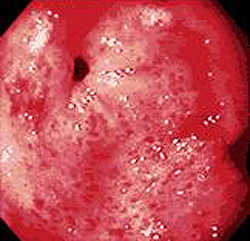

- Эзофагогастродуоденоскопия. Осмотр слизистой при ЭГДС выявляет патогномоничные морфологические признаки заболевания. Для гастрита характерны отечность, гиперемия, эрозии, истончение и атрофия эпителия, участки метаплазии, усиление сосудистого рисунка.

- ФГДС. Эндоскопическая картина дает представление о локализации воспаления, его выраженности и глубине. Для уточнения диагноза и исключения малигнизации берут биопсию слизистой из различных отделов желудка. Определяют уровень кислотности желудочного сока (pH-метрия).

При остром катаральном гастрите в ходе гастроскопии выявляется утолщение, полнокровие, отечность слизистой оболочки желудка, содержание большого количества слизи, иногда – мелкоточечные поверхностные кровоизлияния. В случае наличия многочисленных сливающихся эрозий говорят об остром эрозивном гастрите. Для микроскопической картины характерна дистрофия и слущивание поверхностного эпителия, серозная экссудация, наличие диффузной инфильтрации, интактность глубоких слоев слизистой и желез желудка.

В некоторых случаях при остром гастрите показана гастроскопия, с помощью которой определяется гиперемия, отечность слизистой, наличие эрозий, внутрислизистых кровоизлияний, иногда – признаки желудочного кровотечения. При неясной этиологии острого гастрита выполняется эндоскопическая биопсия слизистой с морфологическим исследованием ткани.

2. Эндоскопические: наличие отека, гиперемии, кровоизлияний, эрозий, контактная ранимость и кровоточивость слизистой оболочки желудка, атрофия и гиперплазия складок в зависимости от степени активности, этиологического фактора.